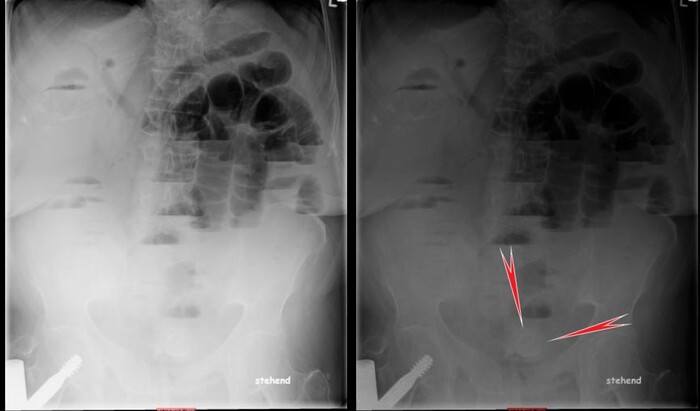

Сделали компьютерную томографию почти всего тела по протоколу множественной травмы (голова, шея, органы грудной клетки + органы брюшной полости включая позвоночник и таз).

Здесь прилагаю только КТ головы, на котором особых патологических изменеий выявлено не было: